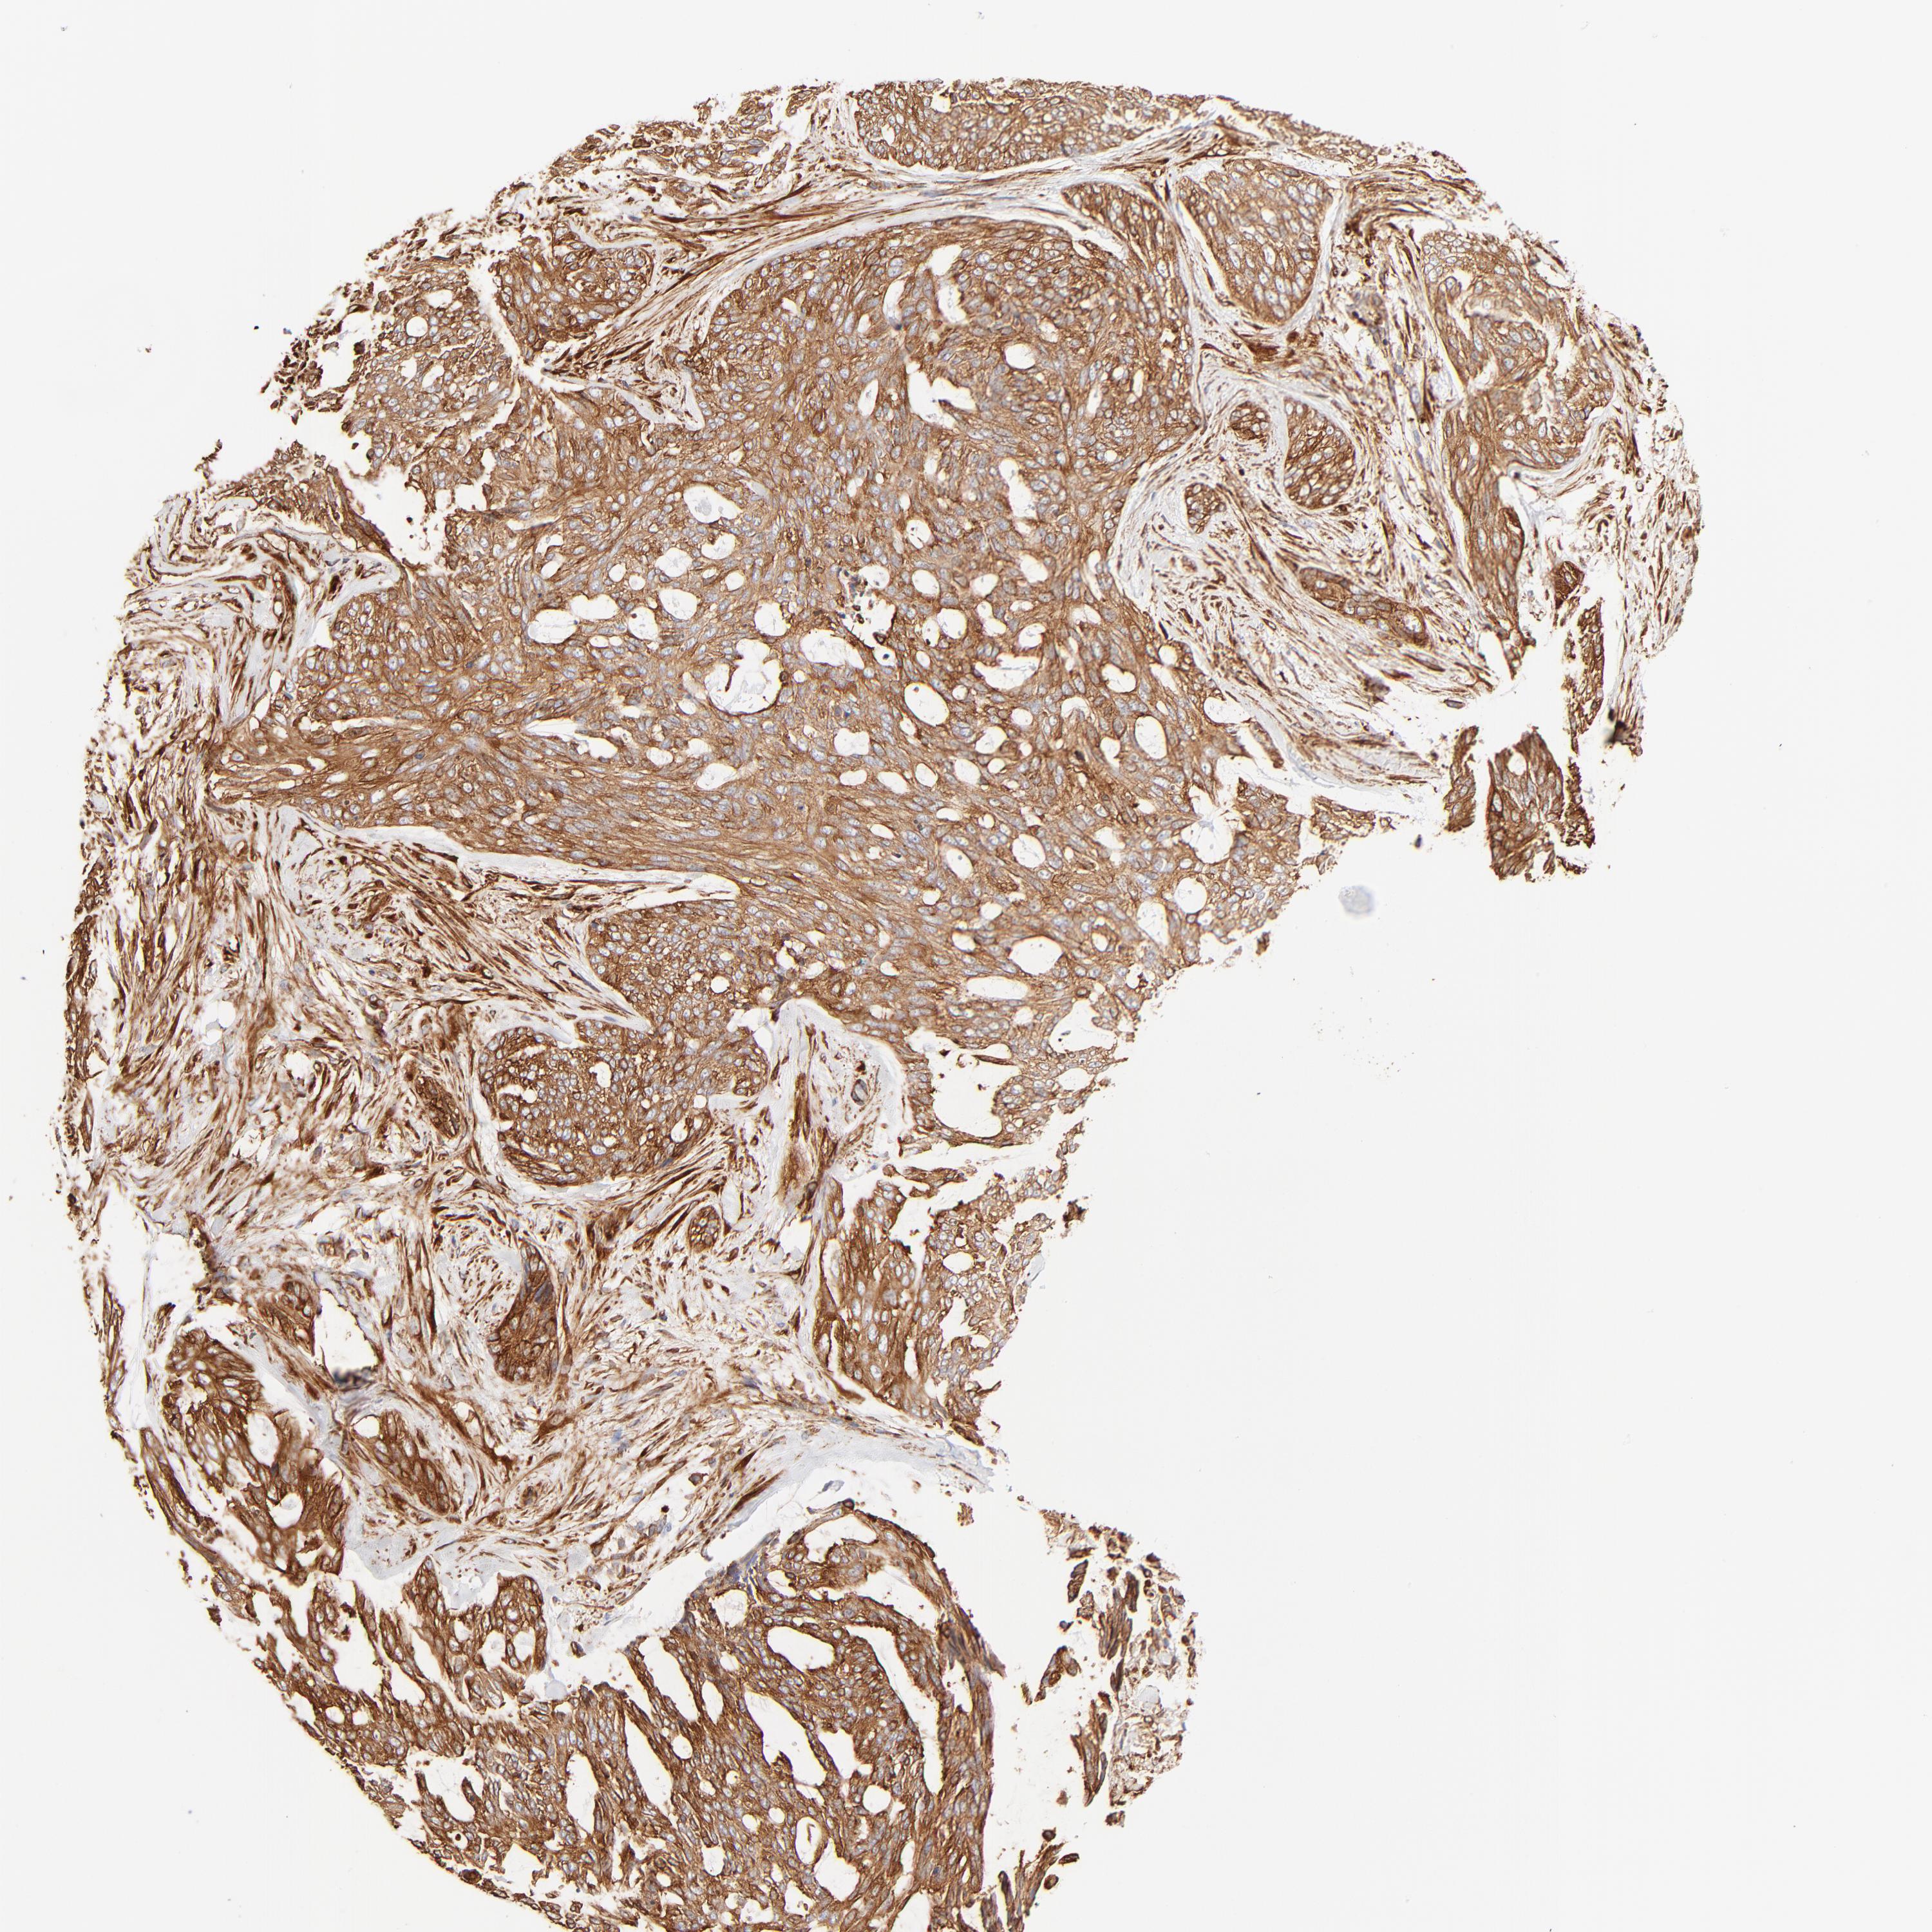

SKIN CANCER - Protein expressioni

A mouse-over function shows sample information and annotation data. Click on an image to view it in a full screen mode. Samples can be filtered based on level of antibody staining by selecting one or several of the following categories: high, medium, low and not detected. The assay and annotation is described here.

Each image is clickable and will lead to virtual microscopy that enables deeper exploration of all samples and also displays staining intensity scores, fraction scores and subcellular localization as well as patient and tissue information for each sample.

Antibody HPA001115

Staining

High

Medium

Low

Not detected

Intensity

Strong

Moderate

Weak

Negative

Quantity

>75%

75%-25%

<25%

None

Location

Nuclear

Cytoplasmic/membranous

Cytoplasmic/membranous,nuclear

Squamous cell carcinoma, NOS

Basal cell carcinoma